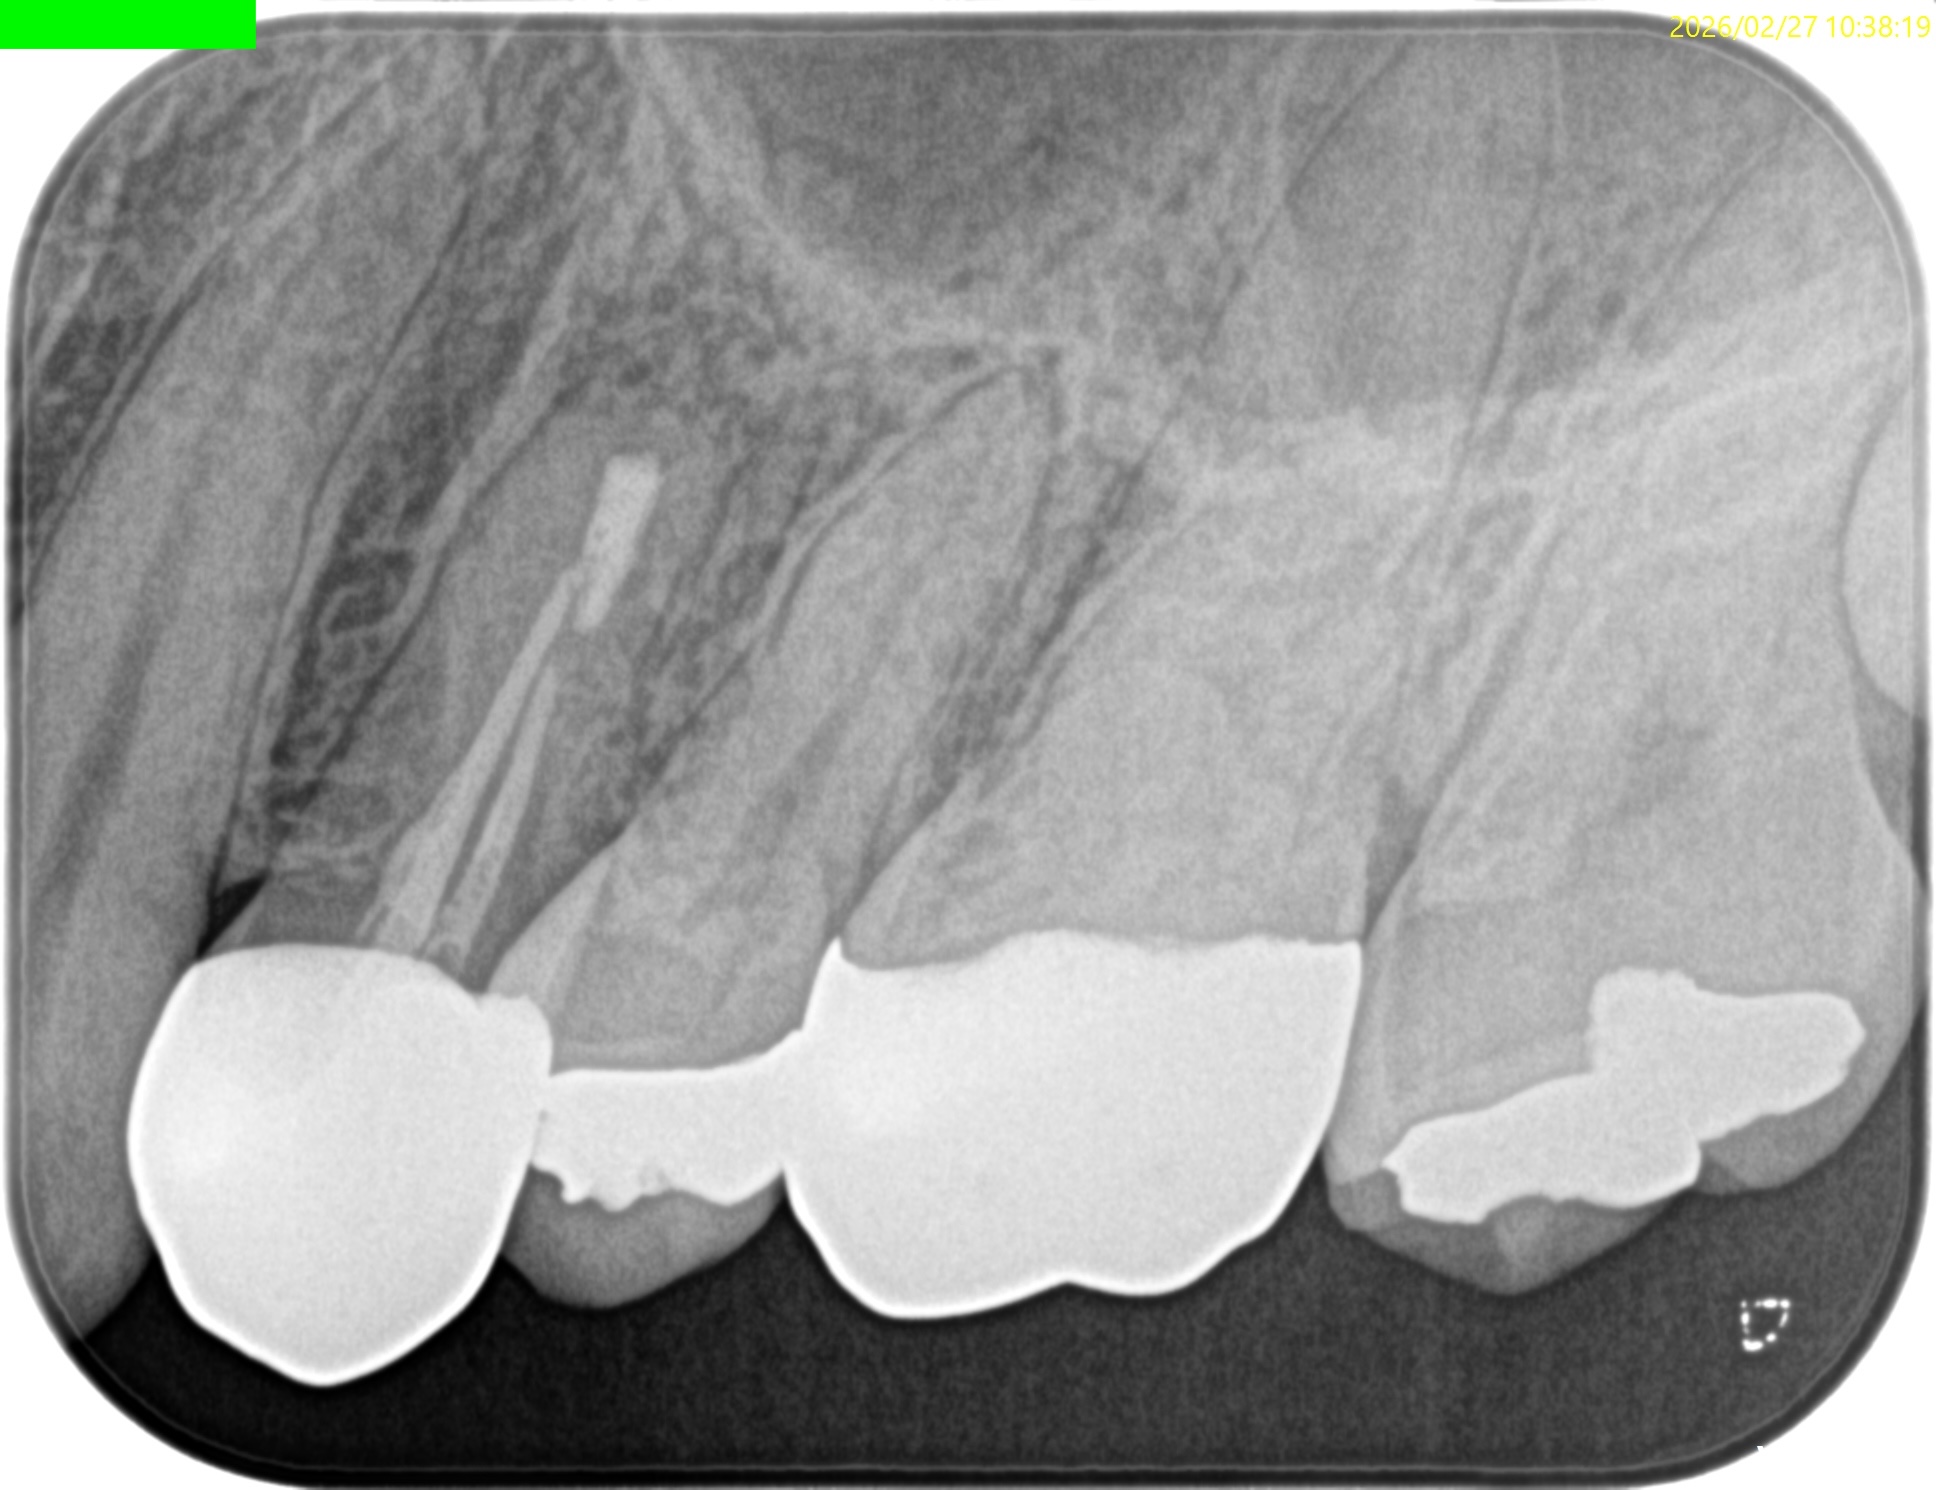

#12 Apicoectomy 1yr recall(2026.2.27)

1年前と比較した。

問題は解決した。

ということでこの日で終診となった。